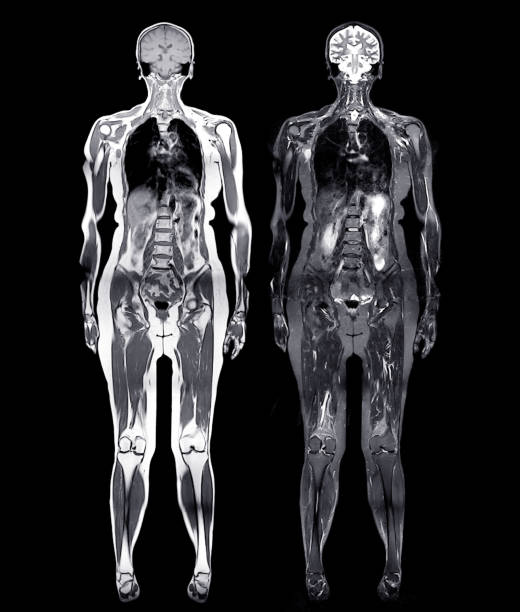

Whole-body MRI screening is fundamentally different from the MRI scans most people experience. When your doctor orders an MRI, it's usually because something's wrong. Maybe you have back pain, or your knee is swollen, or neurological symptoms that need investigation. In those cases, the radiologist knows what to look for. They can focus their expertise and attention on the specific body region and the specific problem.

Elective whole-body MRI works completely differently. The patient isn't sick. There are no symptoms. No red flags. The purpose is purely preventive—to find hidden problems before they cause symptoms. The scan typically covers the head, neck, chest, abdomen, and pelvis, generating hundreds of images that a radiologist must review in detail.

Whole-body screening scans are the opposite. They generate hundreds, sometimes over a thousand images. The radiologist reviewing these scans must mentally scan through all that data looking for anything abnormal. The challenge isn't just volume—it's that they're searching for anything wrong without knowing what might be wrong. They're casting an extremely wide diagnostic net.

MRI has real advantages as a diagnostic tool. It provides exquisite soft tissue detail without using ionizing radiation. For looking at the brain, the spinal cord, joints, and internal organs, MRI is often superior to CT scanning. When a patient has a specific symptom that might be neurological or musculoskeletal, MRI is often the right choice.